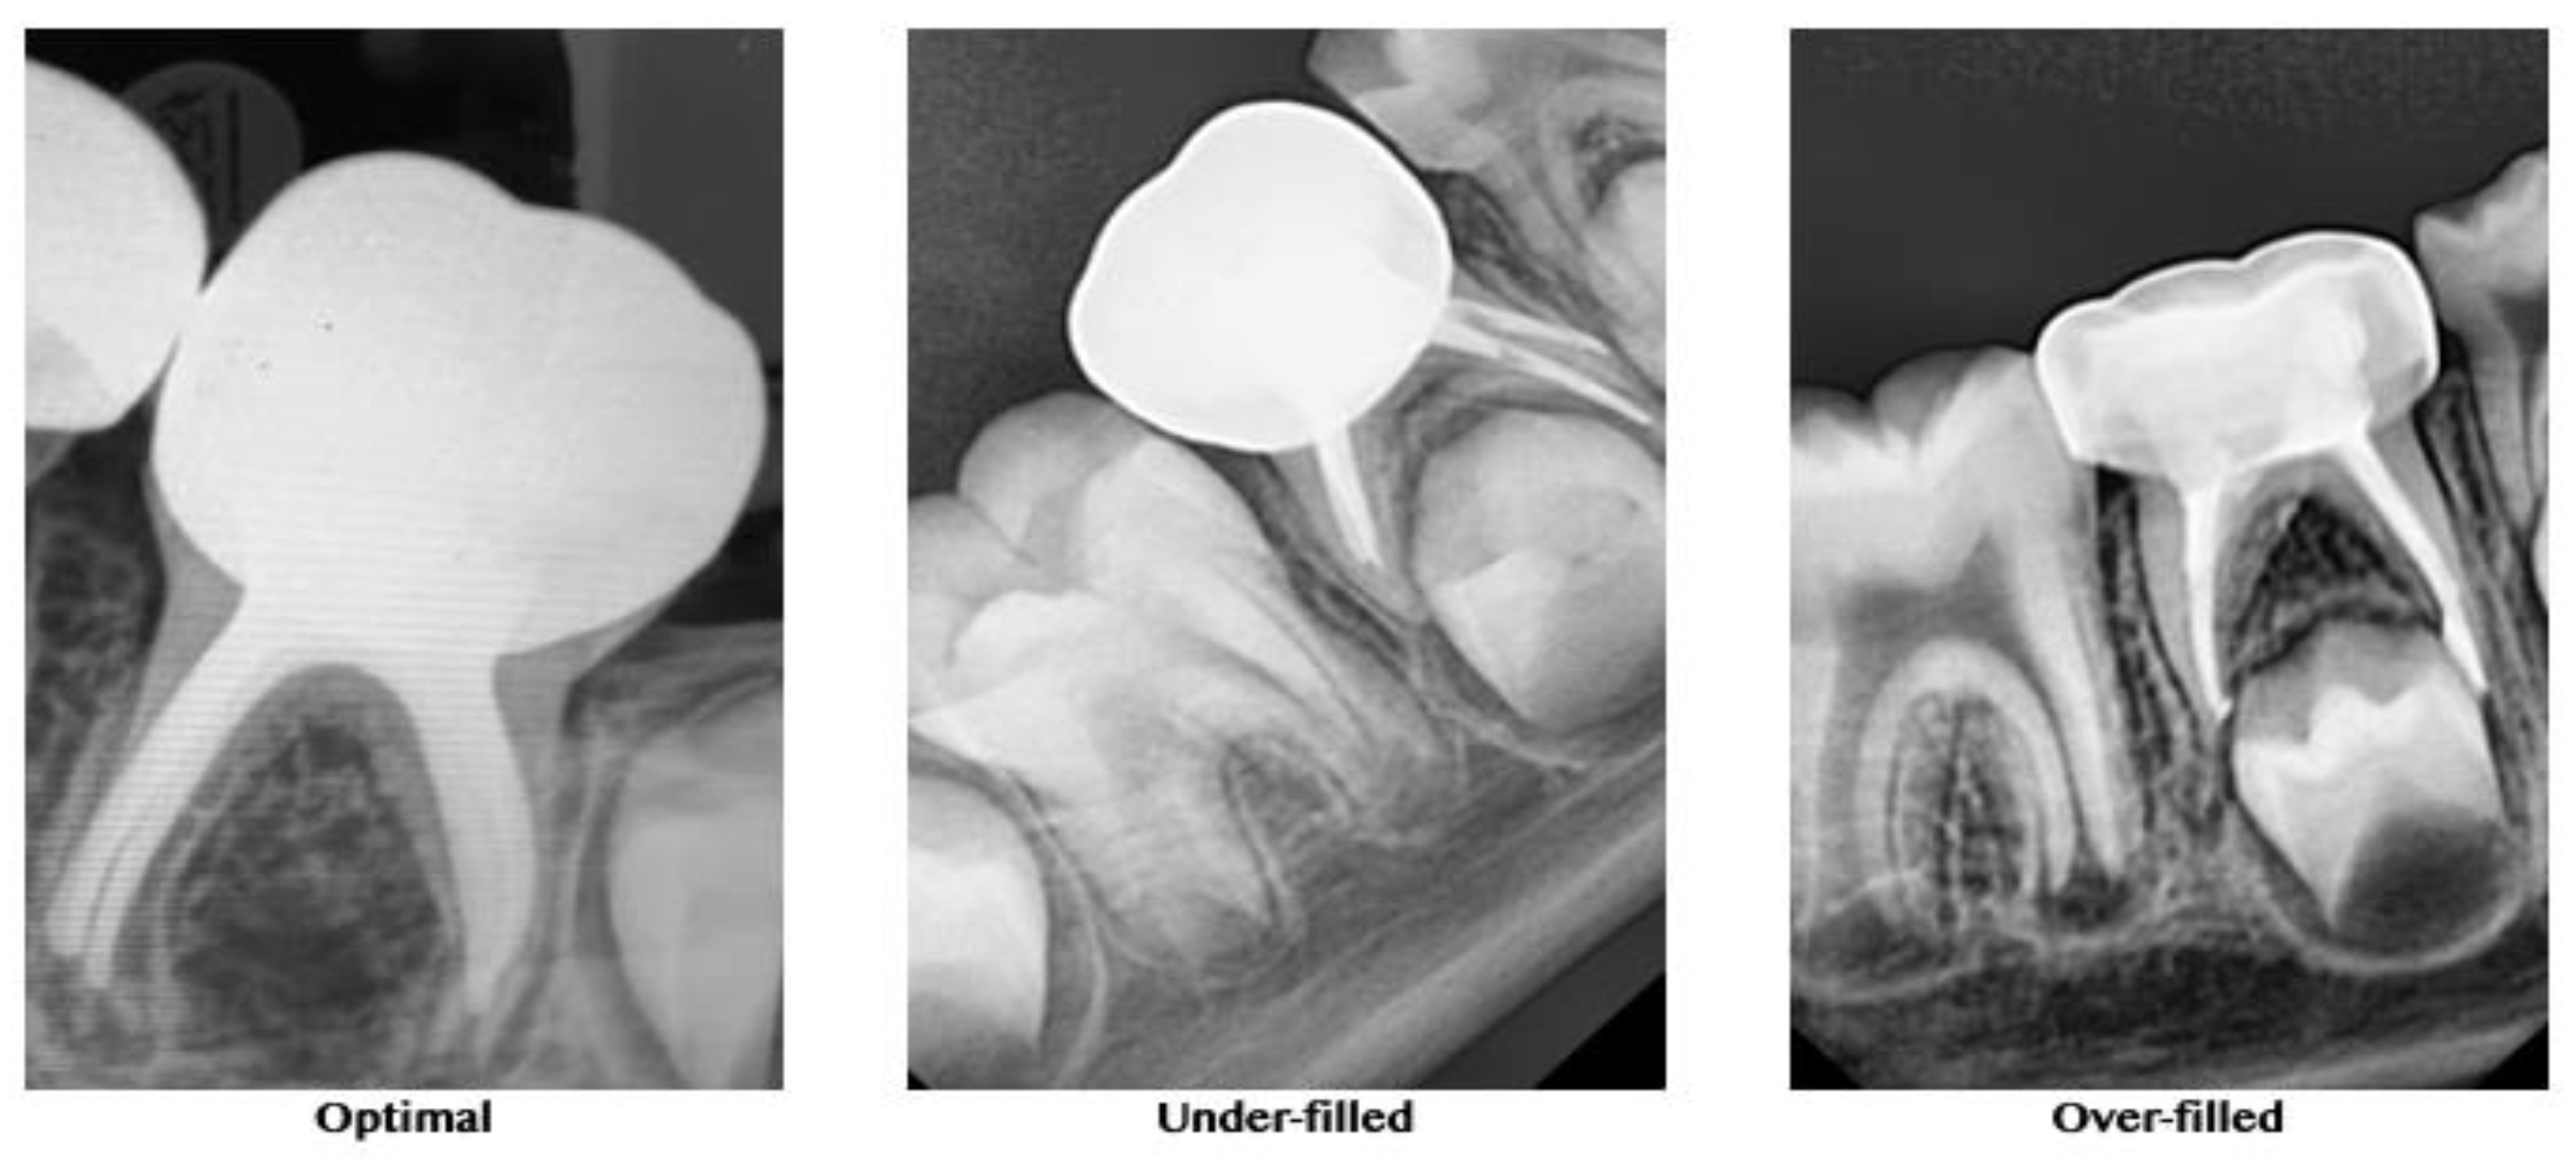

2.3.2. Quality of Obturation

A postobturation radiograph was taken for further evaluation and comparison of the quality of obturation between the groups. The quality of the root canal obturation was recorded, according to O’Riordan and Coll [23] as optimal (1 mm short of the apex), underfilled (2 mm short of the apex), or overfilled (beyond the apex) (Figure 3).

Figure 3. Representative radiographs for the quality of obturation.

3.2. Quality of Obturation

In the XP-endo Shaper group, 19 of the 25 teeth were optimally filled, 2 were underfilled, and 4 were overfilled. In the Kedo-S group, 15 of the 25 teeth were optimally filled, 3 were underfilled, and 7 were overfilled. Finally, in the hand K-file group, 12 of the 25 teeth, were optimally filled, 8 were underfilled, and 5 were overfilled. The results of the quality of obturation are presented in Table 3. The teeth treated with the XP-endo Shaper exhibited significantly better obturation results compared to the other groups (p < 0.01, Chi-square test).

Evaluating the quality of obturation in the present study was limited to the method proposed by O’Riordan and Coll [22] and used the criteria of optimal (1 mm short of the apex), underfilled (2 mm short of the apex), or overfilled (beyond the apex). Obturation in the current study was carried out using Metapex, an iodoform-based calcium hydroxide cement. This cement possesses better resorbing ability and disinfectant properties compared to conventional zinc oxide eugenol cement. Additionally, it is resorbed by macrophages faster than the primary root [29]. This cement is advantageous, exhibiting no foreign body reaction when extruded into furcal or apical areas when used for obturation. There are no reports of any effect of the extruded Metapex on permanent tooth buds to date. It has also been observed that the extruded cement usually resorbs within 1–2 weeks [30]. The present finding that root canals instrumented with the XP-endo Shaper allowed a more frequent (76%) optimal obturation result, according to the above criteria, may be explained by previous ex vivo studies of this adaptive file. The ability of this file to adequately instrument and clean the canals of permanent teeth with an oval cross-section has been studied using microCT [20,27,31,32]. It has been demonstrated that the XP-endo Shaper resulted in better 3D instrumentation than rotary files, affecting a higher percentage of the root canal walls [20,27,31,32]. It could be that a cleaner canal, without debris remnants in its recesses, is easier to obturate with the method used in the present study.